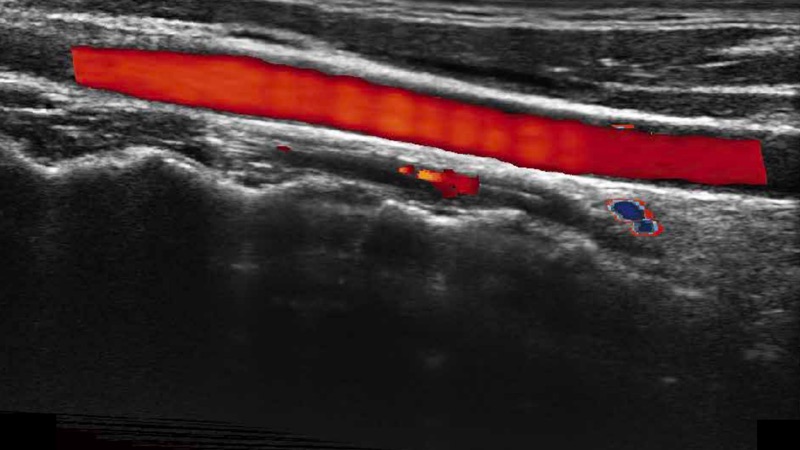

高分辨率血流成像技術(shù)提高了對(duì)低速血流信號(hào)的檢測(cè)能力。在提高空間分辨率的同時(shí),也克服了血流外溢現(xiàn)象,為用戶提供更加真實(shí)的血流動(dòng)力學(xué)信息。